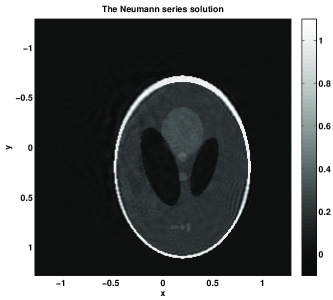

Figure 3: T=2T02.3535𝑇2subscript𝑇02.3535T=2T_{0}\approx 2.3535. The time T𝑇T is slightly above the stability threshold T1/2subscript𝑇12T_{1}/2 but below T1subscript𝑇1T_{1}. The error of the NS solution is 6.63%percent6.636.63\% with k=8𝑘8k=8 (999 terms) of the series vs. error 37.76%percent37.7637.76\% for the TR one. Since T<T1𝑇subscript𝑇1T<T_{1}, the TR solution does not recover the correct size of the jumps — they are recovered with amplitudes ranging from 1/2121/2 to 111, and for many of them, it is just 1/2121/2; this is clear from the slice diagrams. In contrast, the NS solution has the right amplitudes and would improve with more terms.

Figure 3: Example 1 with the non-trapping speed c1subscript𝑐1c_{1}. Case 2: T=4T0𝑇4subscript𝑇0T=4T_{0}. (a): the boundary distance map. (b): the exact initial condition. (c): the time reversal solution. (d): the Neumann series solution. (e): x𝑥x-slices of the time reversal solution (continuous line) and the exact solution (a dashed line). (f): x𝑥x-slices of the Neumann series solution (continuous line) and the exact solution (a dashed line). (g): y𝑦y-slices of the time reversal solution (continuous line) and the exact solution (a dashed line). (h): y𝑦y-slices of the Neumann series solution (continuous line) and the exact solution (a dashed line).